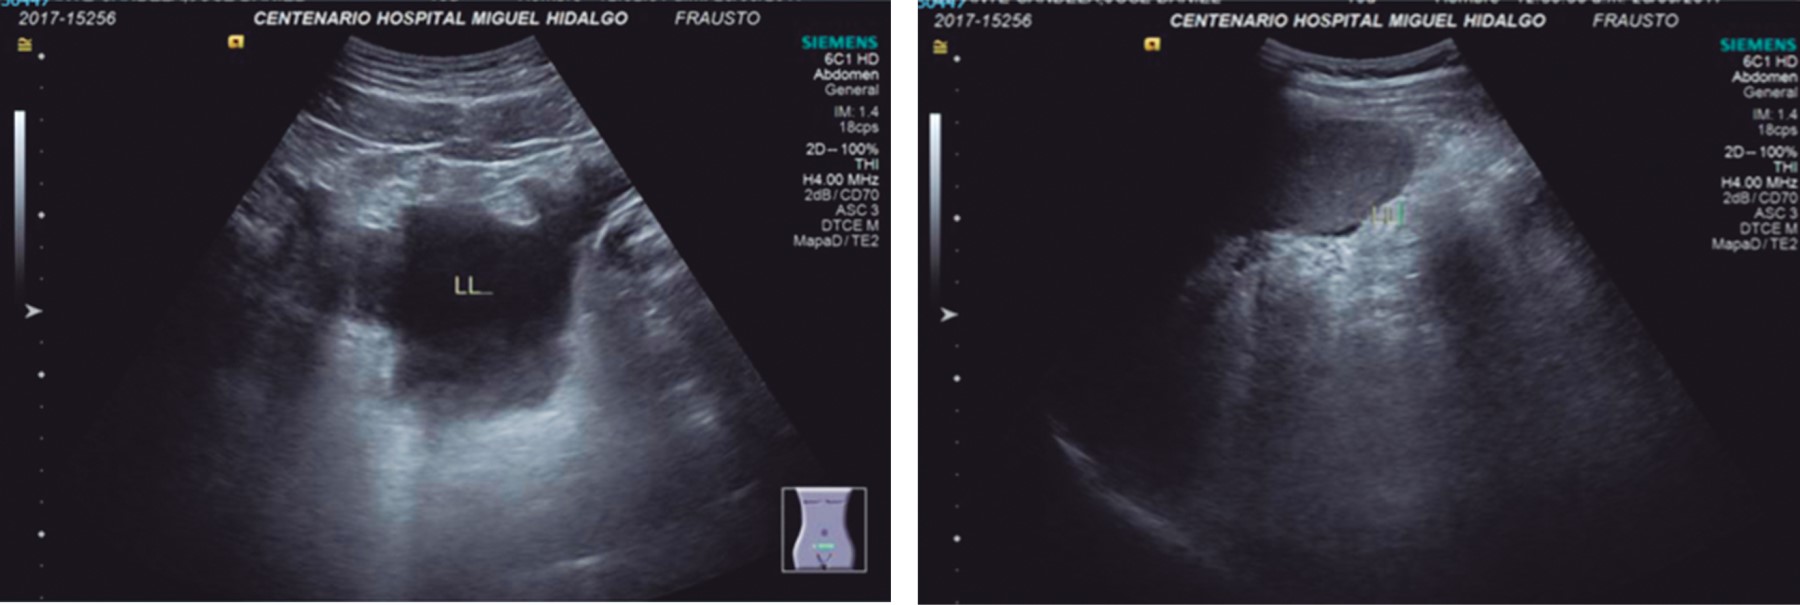

The abdominal ultrasound showed free fluid in subhepatic, peri splenic, and para vesical recesses (Figure 1).

Figure 1